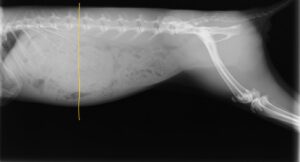

実際の症例

半日前から食欲低下、うんちが出なくなって来院したうさぎです。

レントゲンを撮ると、黄色線が最後肋骨であり、本来はここまでに胃のサイズが収まってほしいのですが、それを大きく出ています。

そして、入院し、治療した翌日のレントゲンが下です。

胃のサイズが小さくなっているのがわかると思います。

このまま退院し、通院にて数週間で完治しました。